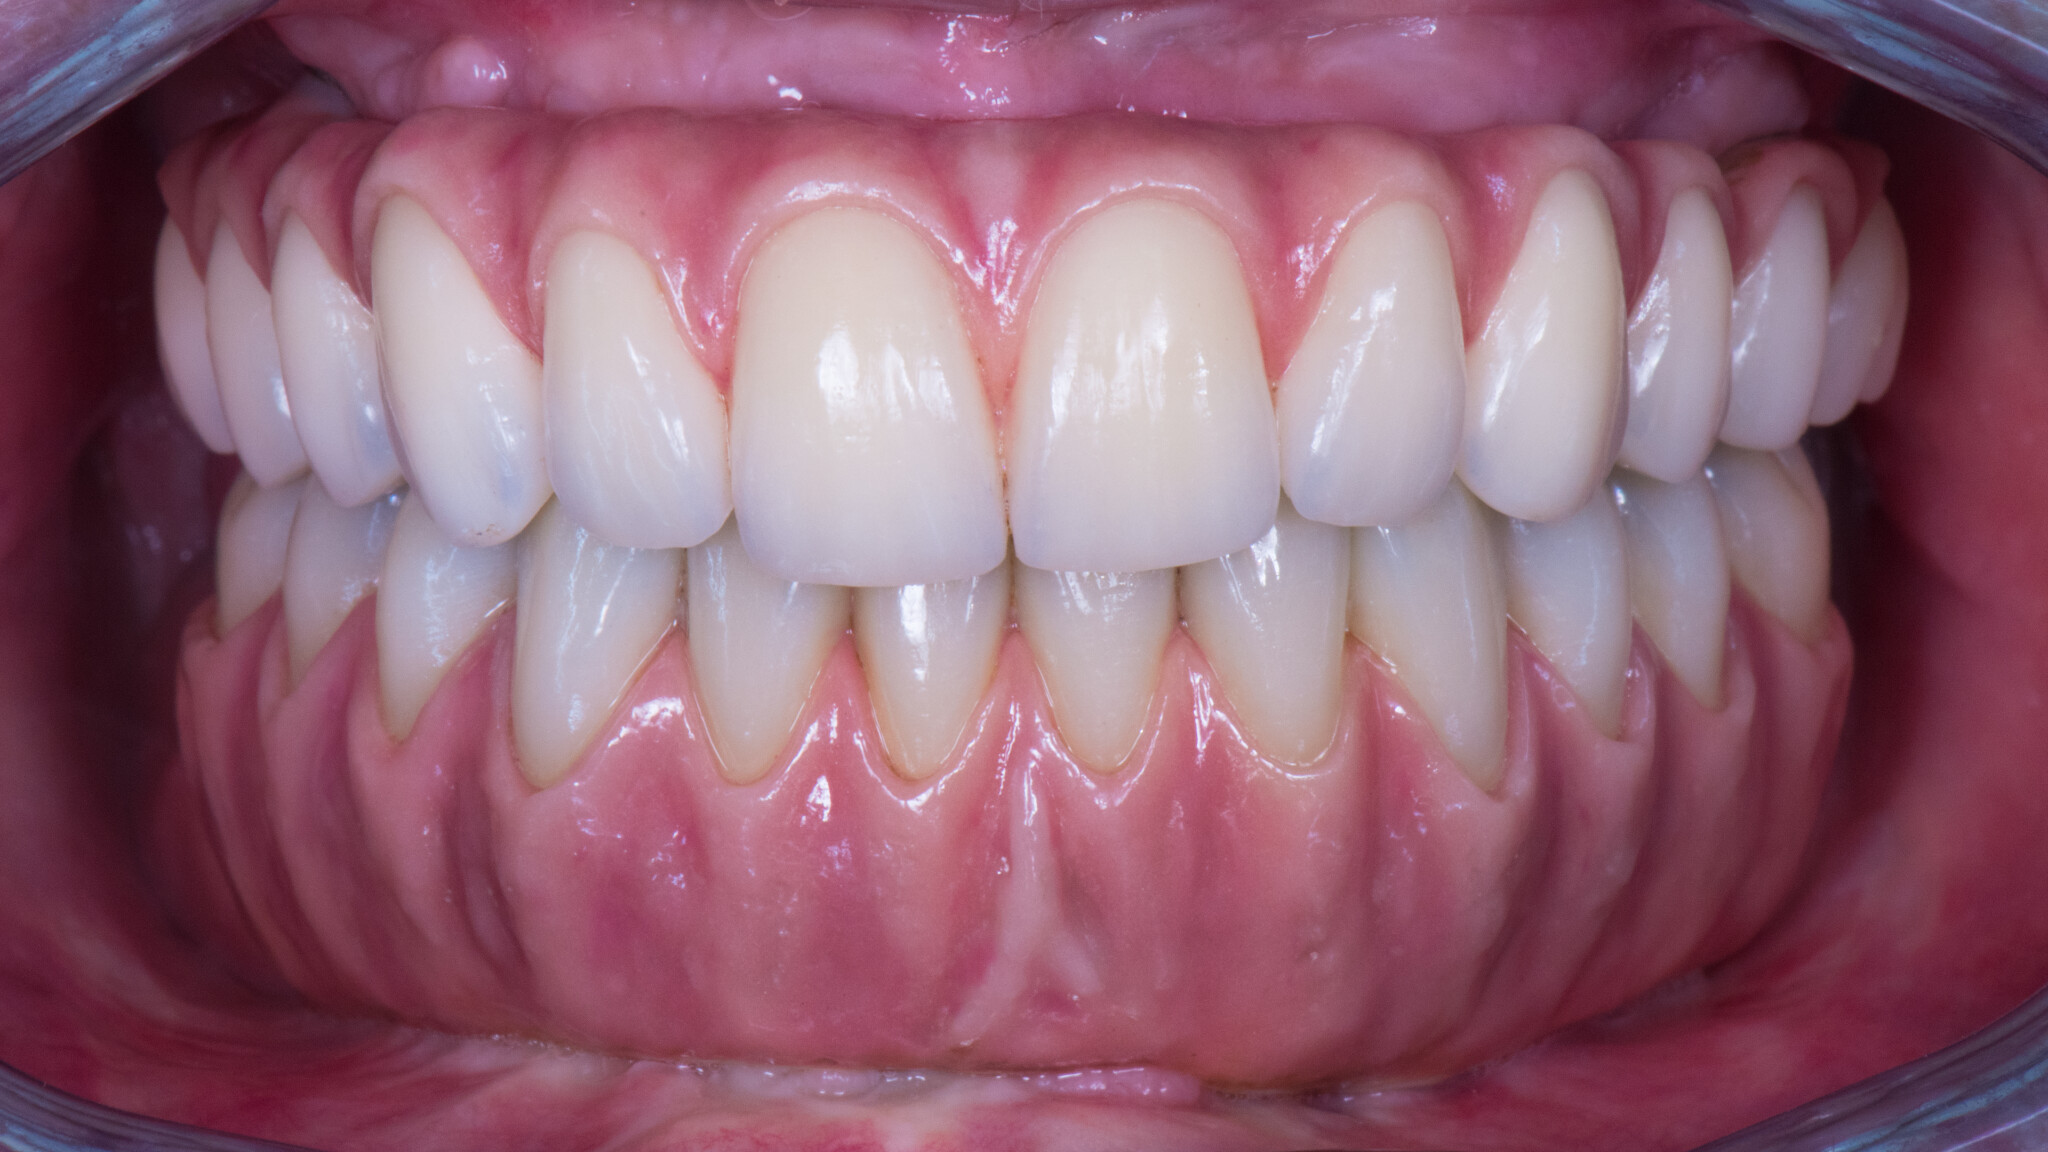

Qui vedi la guarigione a 3 mesi:

L’impronta:

e il lavoro finito.